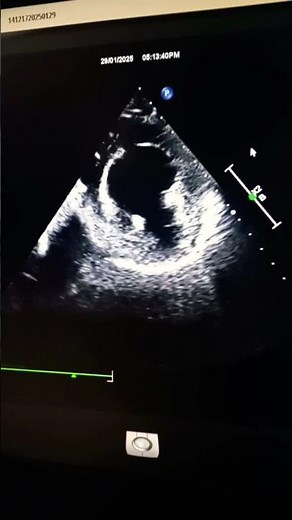

3CH View Hypokinesia of Anterior and Anteroseptum Segments #2decho #echocardiography #echoeducation

🫀 3CH View – Hypokinesia of Anterior and Anteroseptum Segments 🔍 What It Shows: The apical 3-chamber view (also called PLAX-like view from the apex) lets you visualize: Left ventricular anterior wall Anteroseptum Left ventricular outflow tract (LVOT) Aorta and mitral valve Hypokinesia here means the anterior and anteroseptal segments ...